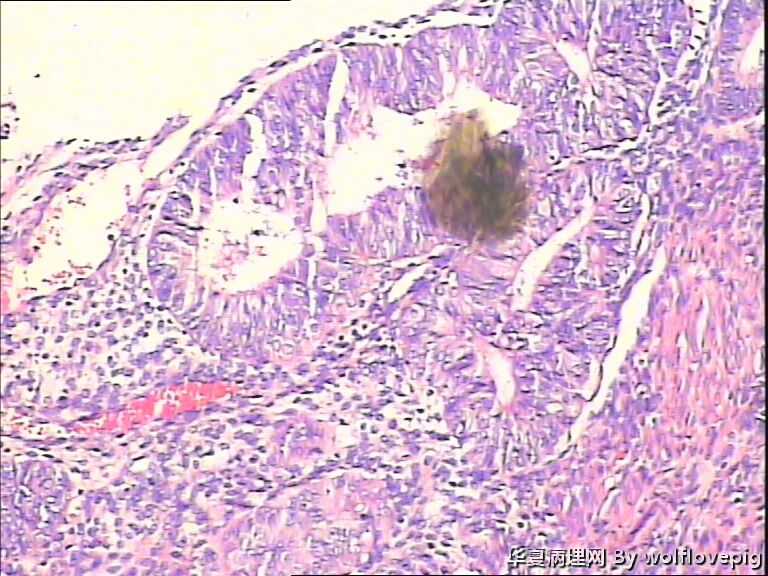

求助,子宫内膜!

48y

• 求助,子宫内膜!图1

图1